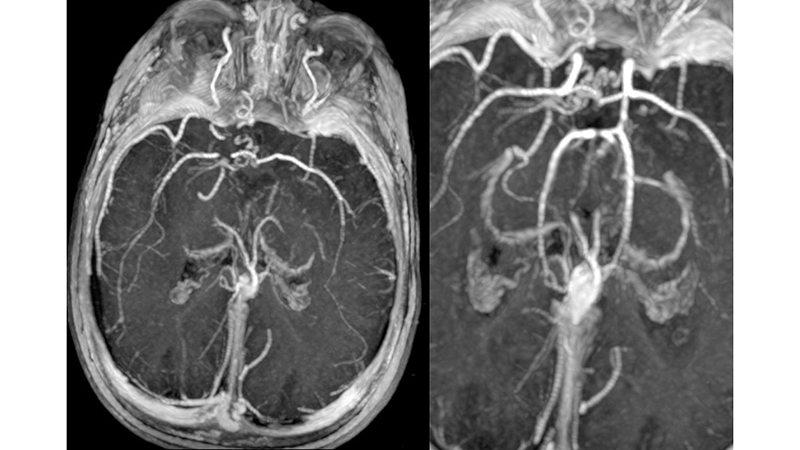

- Στην μαγνητική αγγειογραφία βλέπουμε υποσκληρίδιο αιμάτωμα στο δρέπανο

- και οπισθιοπλάγιους τροφοφόρους κλάδους από τις οπίσθιες εγκεφαλικές αρτηρίες.